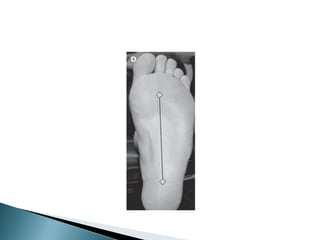

 CALCANEOS

Área plantar proximal

Área plantar media

Pie lateral

Pie distal

Cara posterior del calcáneo hasta la

mitad de la longitud de la cara plantar

del pie

Irrigada por ramas de la arteria dorsal

del pie que se anastomosan con la

plantar lateral

ZONA LIMITROFE, DOS TERCIOS

DISTALES DE LA APONEUROSIS

PLANTAR

RAMAS DE LA PLANTAR MEDIA,

LATERAL Y PROFUNDA

REGION LATERAL HASTA LA

APONEUROSIS PLANTAR EN TERCIO

MEDIO DE LA CARA PLANTAR DEL PIE

IRRIGADO POR LA DORSAL DEL PIE Y

PORCION DISTAL DE LA CARA

PLANTAR HASTA LA PLANTAR MEDIA

ANASTOMOSIS DE LA RAMA PROFUNDA DE

LA ARTERIA DORSAL Y EL COMPONENTE

TRANSVERSO PROFUNDO DE LA PLANTAR

LATERAL Y UNA RAMA DE LA PLANTAR

INTERNA